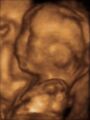

3D ultrasound of 3-بوصة (76 mm) fetus (about 14 weeks gestational age)

Obstetric ultrasonography is routinely used for dating the gestational age of a pregnancy from the size of the fetus, determine the number of fetuses and placentae, evaluate for an ectopic pregnancy and first trimester bleeding, the most accurate dating being in first trimester before the growth of the foetus has been significantly influenced by other factors.[24] Ultrasound is also used for detecting congenital anomalies (or other foetal anomalies) and determining the biophysical profiles (BPP), which are generally easier to detect in the second trimester when the foetal structures are larger and more developed.[25] Specialised ultrasound equipment can also evaluate the blood flow velocity in the umbilical cord, looking to detect a decrease/absence/reversal or diastolic blood flow in the umbilical artery.[26]

X-rays and computerized tomography (CT) are not used, especially in the first trimester, due to the ionizing radiation, which has teratogenic effects on the foetus.[27] No effects of magnetic resonance imaging (MRI) on the foetus have been demonstrated,[28] but this technique is too expensive for routine observation. Instead, obstetric ultrasonography is the imaging method of choice in the first trimester and throughout the pregnancy, because it emits no radiation, is portable, and allows for realtime imaging.[29]

The safety of frequent ultrasound scanning has not been confirmed. Despite this, increasing numbers of women are choosing to have additional scans for no medical purpose, such as gender scans, 3D and 4D scans.[30] A normal gestation would reveal a gestational sac, yolk sac, and fetal pole.[31]

The gestational age can be assessed by evaluating the mean gestational sac diameter (MGD) before week 6, and the crown-rump length after week 6. Multiple gestation is evaluated by the number of placentae and amniotic sacs present.[32]